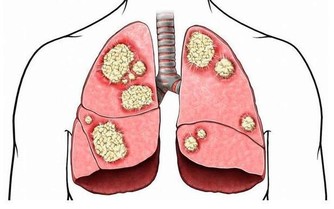

腳部出現青筋,說明血液循環不暢通,但是前期人體並不會出現其他不適應的癥狀。沒有出現不適,不代表完全沒問題。血液循環不暢通,將會導致心臟部位無法及時接受身體回流的血液,繼而影響下一輪供血;還會導致腳部功能退化,出現足部組織壞死的現象。

腳部是身體的最末端,即也是血液循環的最末端,如果腳部出現血液滯留將會影響整個身體的供血工作。血液循環不暢通,將會導致身體的新陳代謝速度減慢,受到影響最大就是消化系統和神經系統。